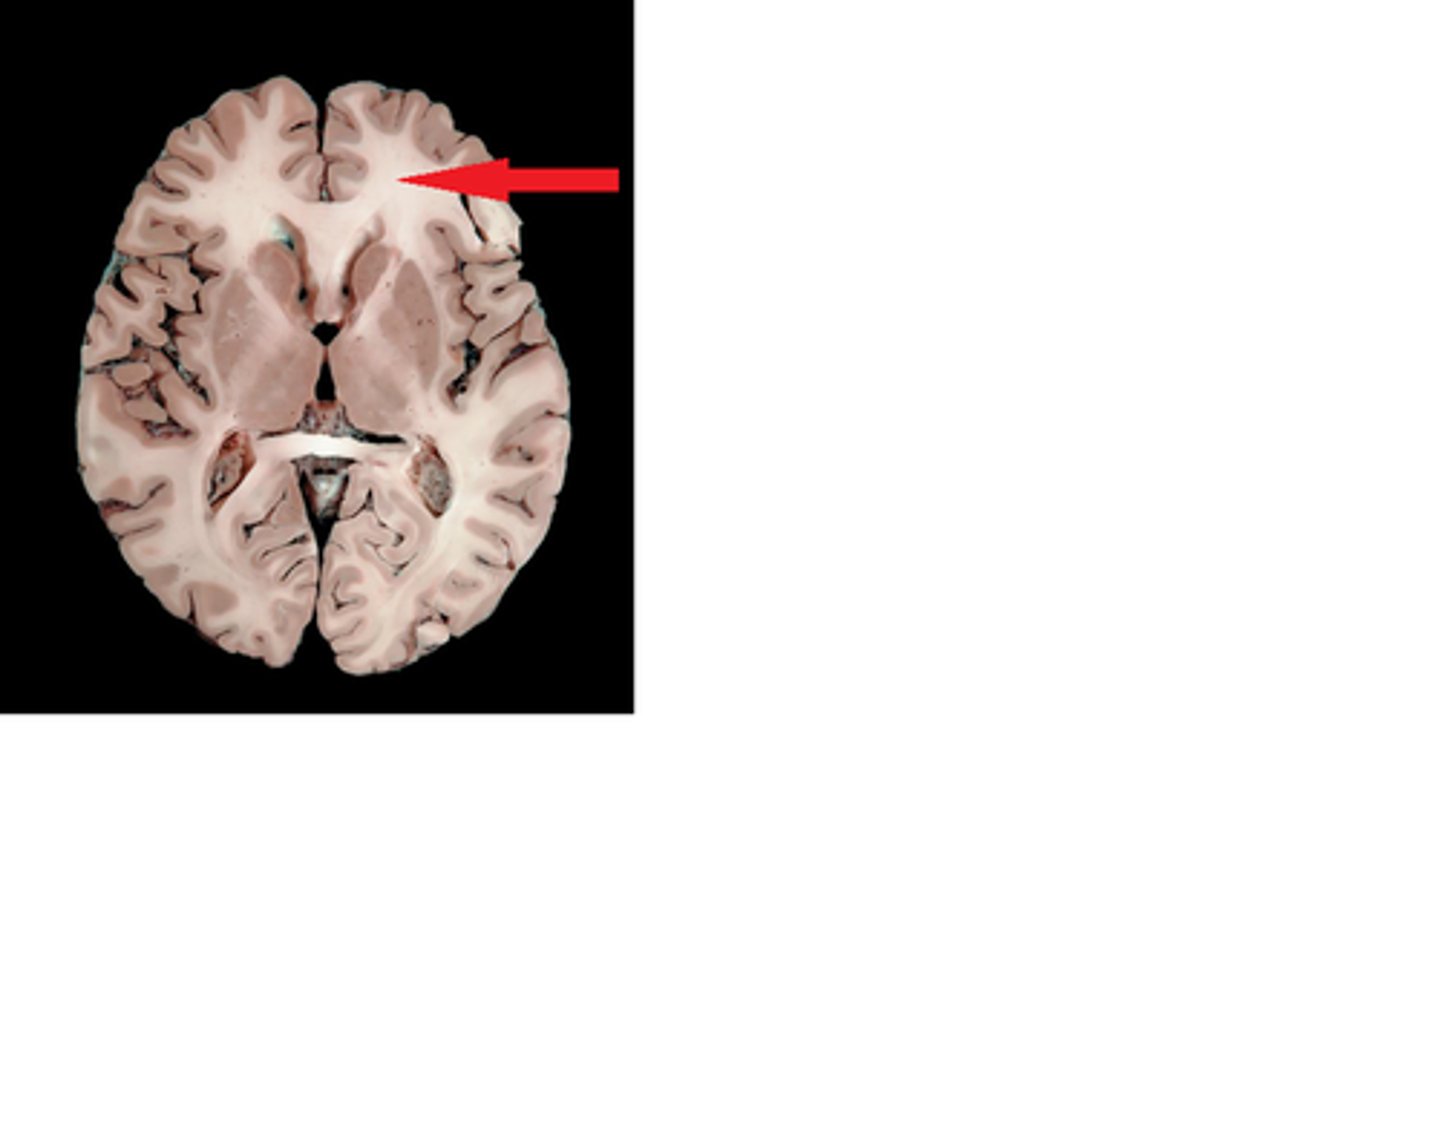

MIdsagittal View of brain

Lateral Ventricle

Third Ventricle

Cerebral Aqueduct

Forth Ventricle

Corpus Callosum

Fornix

Thalamus

Pineal Gland

Superior Colliculi

Inferior Colliculi

Midbrain

Hypothalamus

Cerebral Cortex Gray Matter (nerve cell bodies)

White Matter (myelinated nerve fibers)